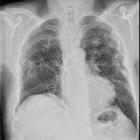

Asbestos-related benign pleural disease

Asbestos-related benign pleural disease forms a large part of asbestos-related lung changes.

The spectrum comprises of:

- pleural effusions: benign asbestos-induced pleural effusions

- can be associated with functional impairment

- usually occur within 10 years of exposure but can also develop much later

- pleural thickening

- focal thickening: pleural plaques

- calcific pleural plaques

- non-calcific pleural plaques

- diffuse pleural thickening